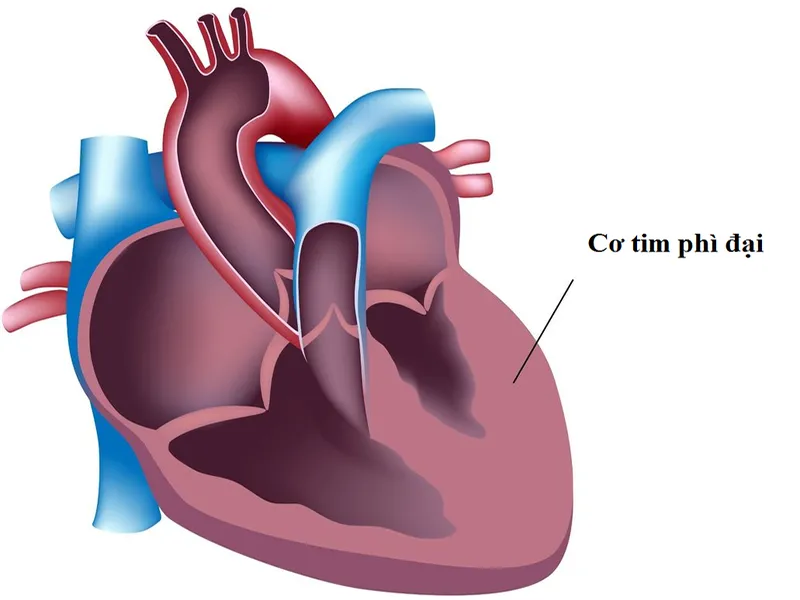

Bệnh cơ tim phì đại là một tình trạng bệnh lý tiềm ẩn có thể gây ra nhiều tương tác nghiêm trọng với sức khỏe. Nhận biết sớm và điều trị đúng cách là rất quan trọng để bảo vệ trái tim của bạn. Hãy...

Bệnh cơ tim phì đại là một tình trạng bệnh lý tiềm ẩn có thể gây ra nhiều tương tác nghiêm trọng với sức khỏe. Nhận biết sớm và điều trị đúng cách là rất quan trọng để bảo vệ trái tim của bạn. Hãy...